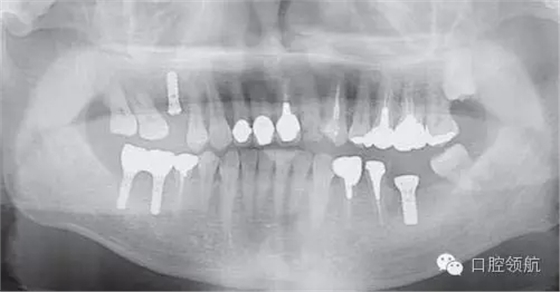

缺損處的近遠中距離較大, 所以植入了StraummanWN(直徑4.8mm×長10mm)的種植體,術(shù)中生命體征穩(wěn)定,無特別事項發(fā)生。術(shù)后,給患者開出用抗生素和止痛藥。1日3次,口服3天的處方。圖3是植入術(shù)后立即拍攝的曲面斷層影像。

圖3 左下頜植入術(shù)后立即拍攝的曲面斷層影像。